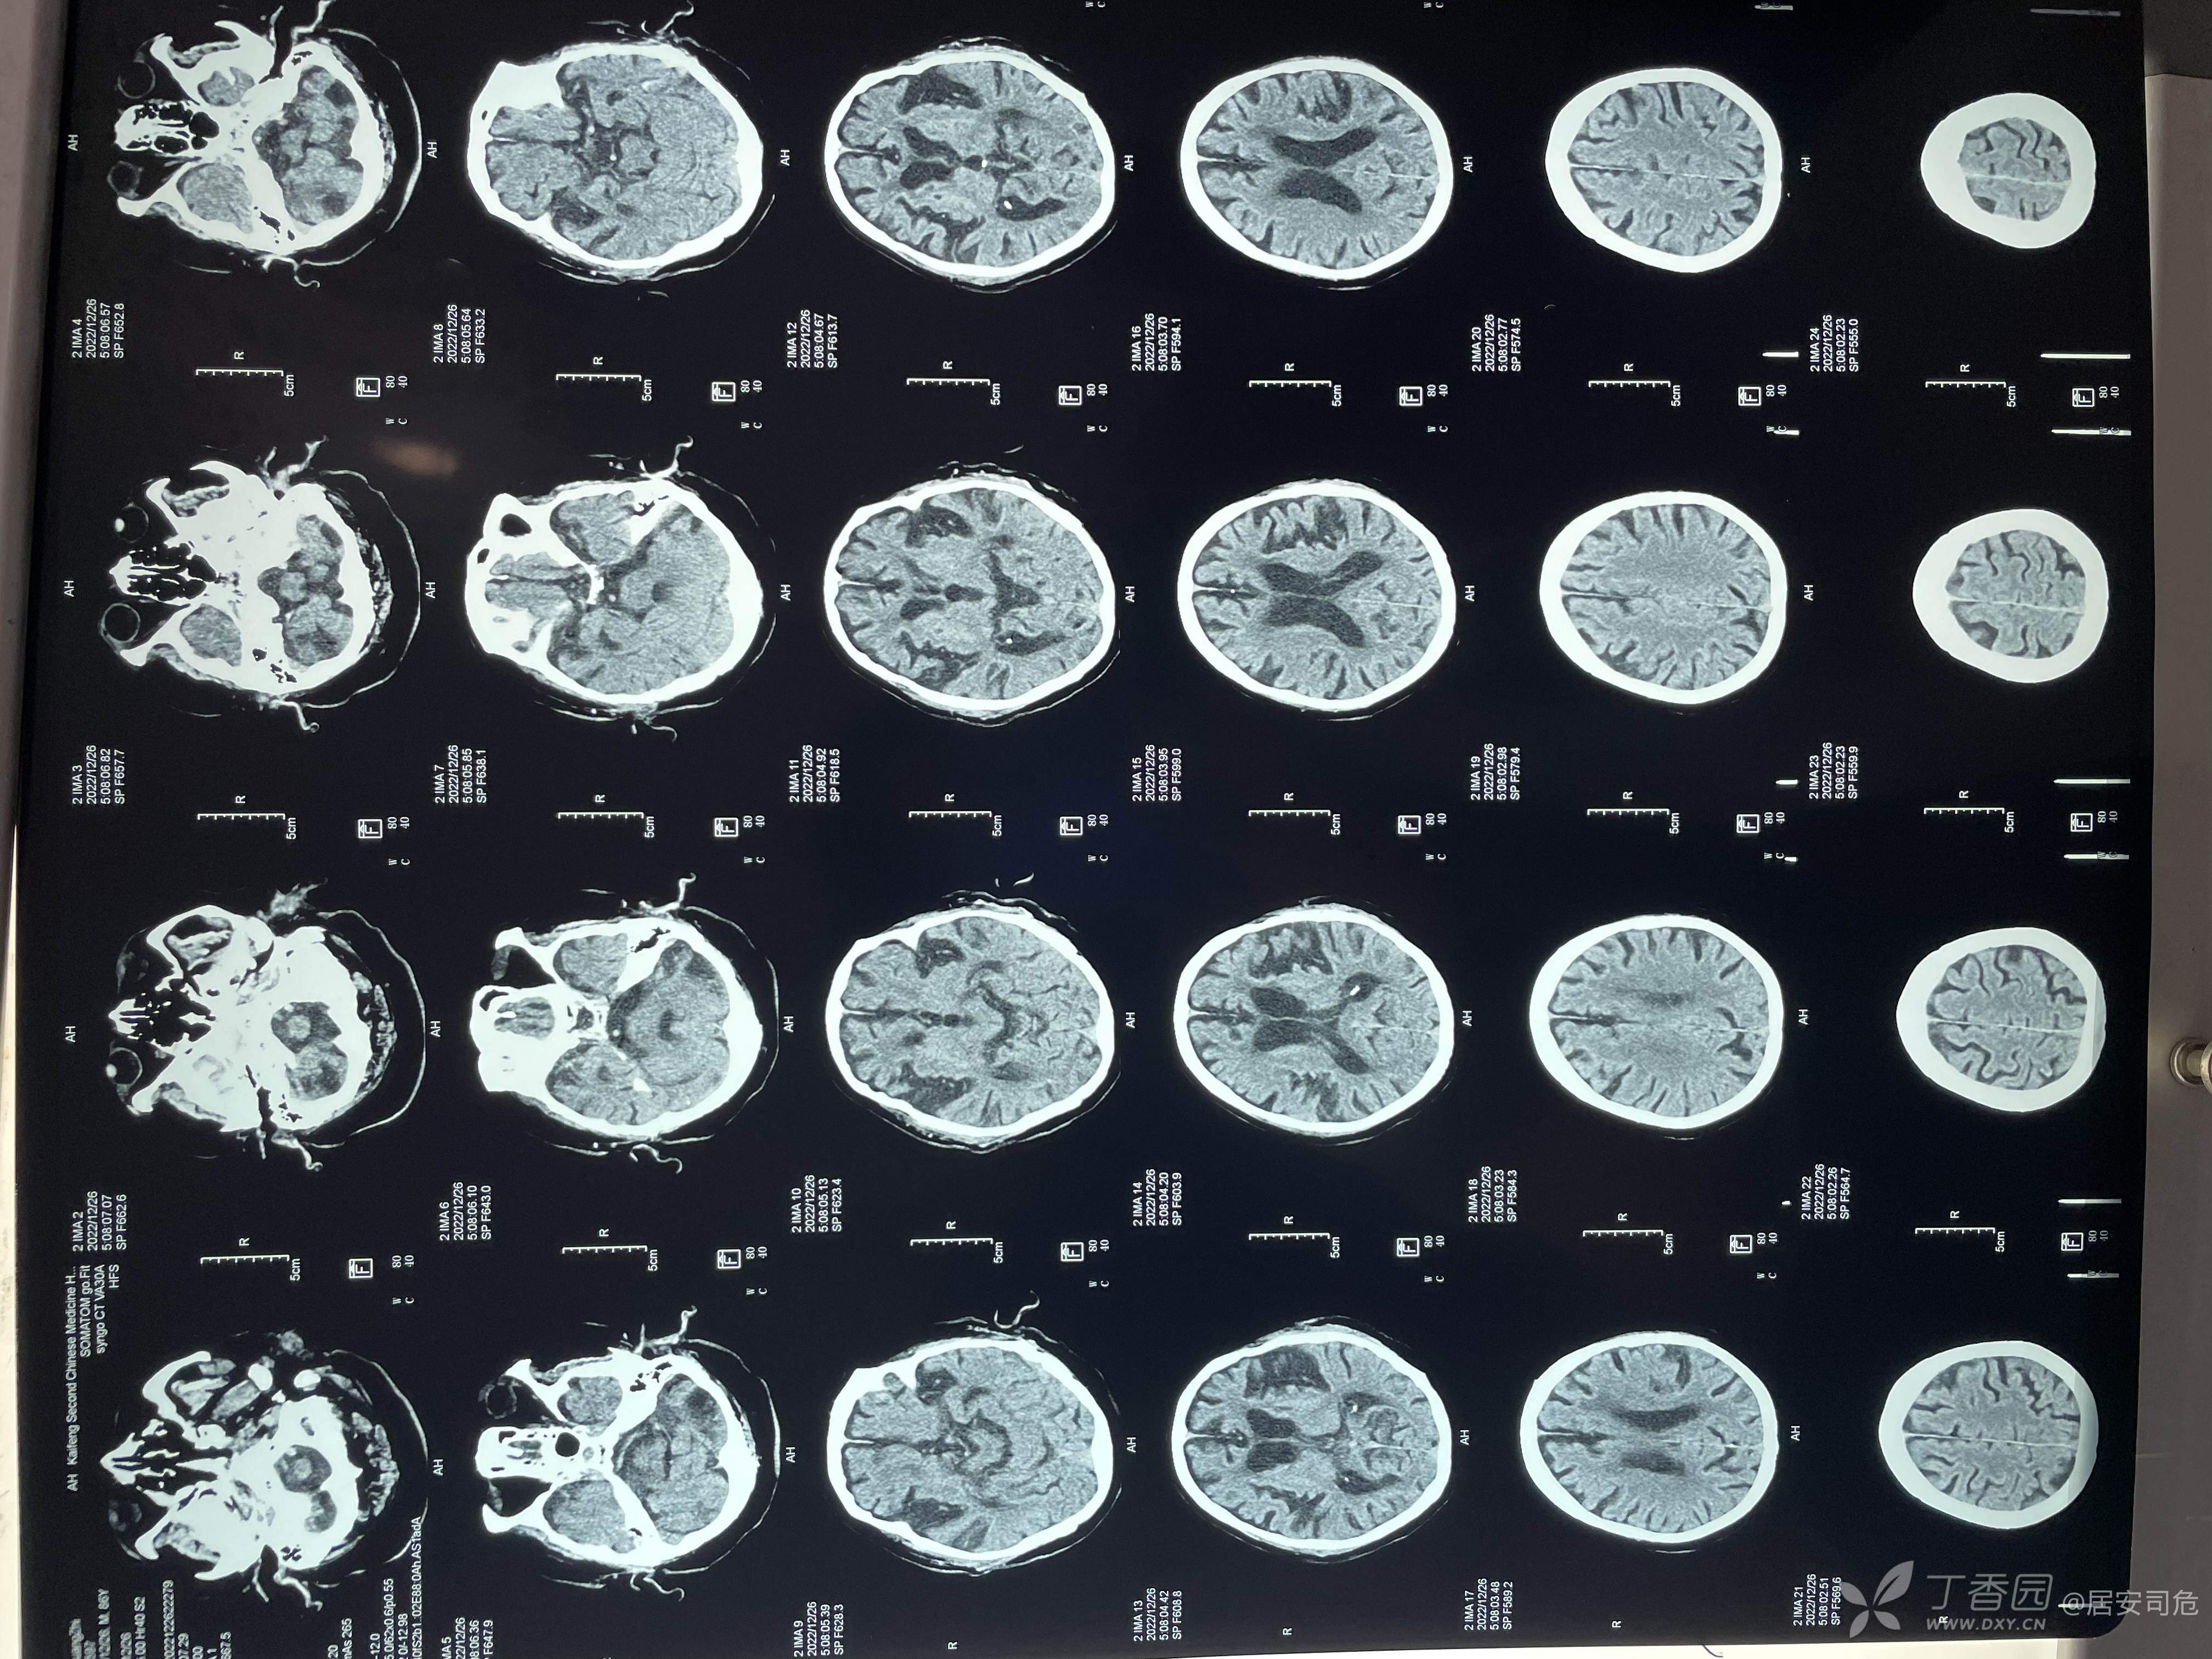

86岁男性,夜间睡眠时突发意识不清,家属发现时口吐白沫,呼之不应,无肢体抽搐及肌肉强直,120急诊查血糖1.0mmol/L,完善胸部CT,头颅CT(下图)对症处理后,意识转清。1周前有咳嗽,咳痰,胸闷症状,无发热,盗汗等,现因呼吸道症状入我院治疗。入院后予以抗生素(头孢呋辛联合莫西沙星),化痰,活血化瘀等治疗。治疗两天,出现定向力障碍,不认识人,近期记忆力下降,睡眠颠倒。四肢肌力肌张力正常,双病理征阴性。入院监测血糖8mmol/L,血压160/90mmHg左右。指脉氧96%,血常规及超敏C反应蛋白基本正常,肝肾功能正常。讨论脑脑功能障碍的原因是什么